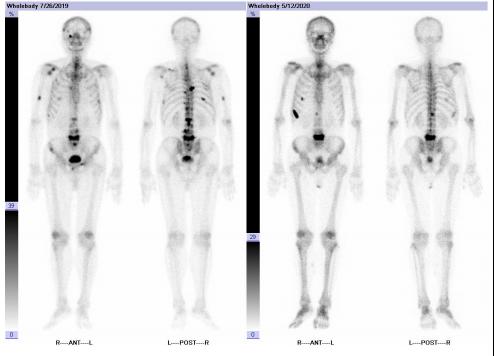

2020年5月13日,复查全身骨显像示:考虑为肿瘤骨转移,与上次检查比较右侧第8前肋为新增病灶,其余病灶数目较前减少。

图5 患者复查骨显像状况

本例患者治疗受到疫情的影响,骨痛事件加重,发现PSA升高,转入mCRPC阶段的时机稍有延迟,但换用醋酸阿比特龙+泼尼松+ADT治疗后,PSA迅速、深度下降,骨转移病灶减弱,体现了阿比特龙对mCRPC阶段患者的良好疗效,后续仍应继续规范化治疗和监测相关指标。